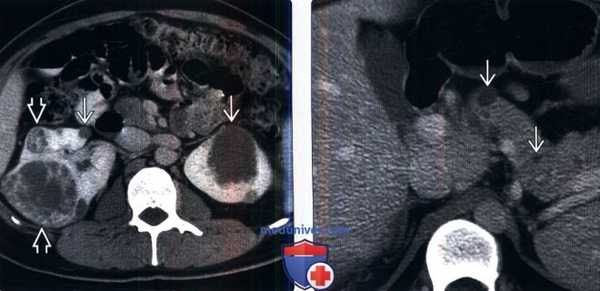

(Слева) КТ с контрастированием, аксиальная проекция: у пациента с болезнью Гиппеля-Линдау выявлены двусторонние кисты почек и множественные сложные кистозные объемные образования с контрастируемыми узелками и перегородками, что позволяет предположить кистозный ПКР. Кисты почек и ПКР - распространенные висцеральные проявления болезни Гиппеля-Линдау.

(Справа) КТ с контрастированием, аксиальная проекция: у данного пациента визуализированы множественные кисты поджелудочной железы.

При скрининговом ультразвуковом исследовании забрюшинного пространства были выявлены изменения обеих почек, которые были интерпретированы как множественные кисты при дообследовании на КТ забрюшинного пространства: множественные кистозные образования обеих почек; в верхнем полюсе левой почки — кистозно-солидное образование, изоденсное паренхиме почки в нативную фазу (40 HU), в артериальную активно накапливающее контраст (до 100 HU), контуры его четкие неровные (рис. 5, 6).

Рис. 5. Пациентка П., 30 лет, с диагнозом «Болезнь Гиппеля−Линдау»: компьютерная томография забрюшинного пространства

Примечание. А — нативная фаза: кисты обеих почек, солидный узел в верхнем полюсе левой почки; Б — артериальная фаза: кисты обеих почек более отчетливы на фоне контрастированной почечной ткани, солидный узел в верхнем полюсе левой почки с неоднородным накоплением контраста опухолью.

Рис. 6. Пациентка П., 30 лет, с диагнозом «Болезнь Гиппеля−Линдау»: компьютерная томография забрюшинного пространства

Примечание. А — нативная фаза: кистозно-солидное образование левой почки; Б — артериальная фаза: кистозно-солидное образование левой почки с неоднородным накоплением контраста опухолью.